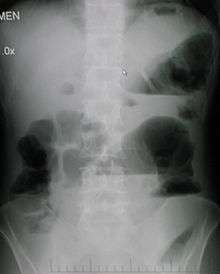

Upright abdominal X-ray demonstrating a small bowel obstruction. Note multiple air fluid levels. | |

Radiological signs of bowel obstruction include bowel distension and the presence of multiple (more than six) gas-fluid levels on supine and erect abdominal radiographs.

Contrast enema or small bowel series or CT scan can be used to define the level of obstruction, whether the obstruction is partial or complete, and to help define the cause of the obstruction.